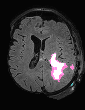

In recent years, data-driven machine learning (ML) methods have revolutionized the computer vision community by providing novel efficient solutions to many unsolved (medical) image analysis problems. However, due to the increasing privacy concerns and data fragmentation on many different sites, existing medical data are not fully utilized, thus limiting the potential of ML. Federated learning (FL) enables multiple parties to collaboratively train a ML model without exchanging local data. However, data heterogeneity (non-IID) among the distributed clients is yet a challenge. To this end, we propose a novel federated method, denoted Federated Disentanglement (FedDis), to disentangle the parameter space into shape and appearance, and only share the shape parameter with the clients. FedDis is based on the assumption that the anatomical structure in brain MRI images is similar across multiple institutions, and sharing the shape knowledge would be beneficial in anomaly detection. In this paper, we leverage healthy brain scans of 623 subjects from multiple sites with real data (OASIS, ADNI) in a privacy-preserving fashion to learn a model of normal anatomy, that allows to segment abnormal structures. We demonstrate a superior performance of FedDis on real pathological databases containing 109 subjects; two publicly available MS Lesions (MSLUB, MSISBI), and an in-house database with MS and Glioblastoma (MSI and GBI). FedDis achieved an average dice performance of 0.38, outperforming the state-of-the-art (SOTA) auto-encoder by 42% and the SOTA federated method by 11%. Further, we illustrate that FedDis learns a shape embedding that is orthogonal to the appearance and consistent under different intensity augmentations.